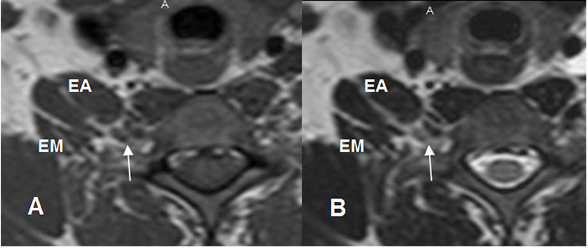

Fig 3. Raíces normales.

A: RM axial en T1 y B: RM axial en T2. Raíces normales (Flechas delgadas), que emergen entre los músculos escaleno anterior (EA) y escaleno medio. (EM).